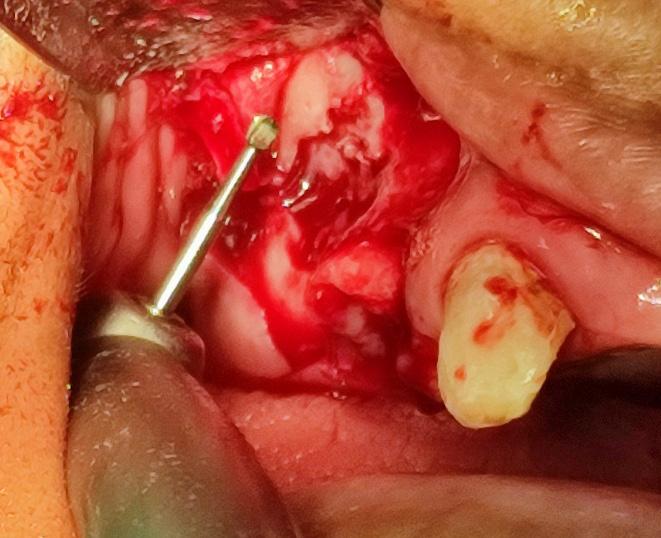

ABSTRACT

Systemic Lupus Erythematosus (SLE) is an autoimmune disease in which organs, tissues and cells are damaged by the exaggerated response of T cells and B cells, loss of immune tolerance against non-specific antigens of the organism. Lupus Enteritis (LE) is defined as vasculitis or inflammation of the small intestine that is diagnosed with the support of imaging and/or biopsy findings. Intestinal pneumatosis (PI) is a rare disease characterized by the presence of intramural gas in the gastrointestinal tract, associated with various clinical conditions, such as pulmonary diseases, gastrointestinal diseases and traumatic injuries, as well as autoimmune disorders.

A bibliographic search was carried out in databases such as PubMed, Nature, Elsevier and Google Scholar, with keywords such as “intestinal pneumatosis” and “lupus enteritis”.

Case presentation: Female patient with a history of surgery for intestinal obstruction, then returned due to a clinical picture of more or less 6 days, in poor general condition with hypotension 80/50 mmHg that did not improve with the administration of crystalloids, for which admission to the Intensive Care Unit (ICU) is indicated, with the need for vasopressors, interconsultation with surgery is carried out where it is decided to perform an exploratory laparoscopy, ruling out intestinal vascular compromise, after starting corticosteroids, the patient shows improvement and is discharged to the general ward in good condition and later home discharge.

Conclusion: Intestinal pneumatosis due to lupus enteritis is one of the rare manifestations with non-specific symptoms where prompt diagnosis and treatment is required. Giving a good response to corticosteroids and avoiding unnecessary surgical interventions.

Key words: Intestinal pneumatosis, lupus erythematosus, lupus enteritis,

INTRODUCCIÓN

El Lupus Eritematoso Sistémico (LES) es una enfermedad autoinmunitaria en la cual los órganos, tejidos y células se dañan por la respuesta exagerada de las células T y células B, perdida de la tolerancia inmune contra antígenos no específicos del organismo (1). La producción y eliminación defectuosa de anticuerpos, también depósitos de complejos autoinmunes, complemento y activación de citocinas (1), permiten el debut con las manifestaciones clínicas con la presencia de un 95 % de compromiso musculo esquelético, un 80 % cutáneas y con menos frecuencia las digestivas, 40 % (3), siendo así que la última que se menciona no forma parte del criterio diagnóstico

por la infrecuencia de los síntomas; la afectación gastrointestinal es una queja común que se observa en el 40 a 60 % de los pacientes con LES; se han descrito manifestaciones gastrointestinales clínicamente reconocidas en el 8 al 10% de los pacientes; por otro lado, los estudios de autopsia, informan hallazgos de compromiso gastrointestinal en el 60 a 70 % de los pacientes lo que sugiere un compromiso subclínico o no reconocido (11).

La Enteritis Lúpica (EL) es definida como una vasculitis o inflamación del intestino delgado con apoyo de hallazgos de imagen y/o biopsia; en la cual la tomografía es el examen de elección que nos muestra una mayor visibilidad de los vasos